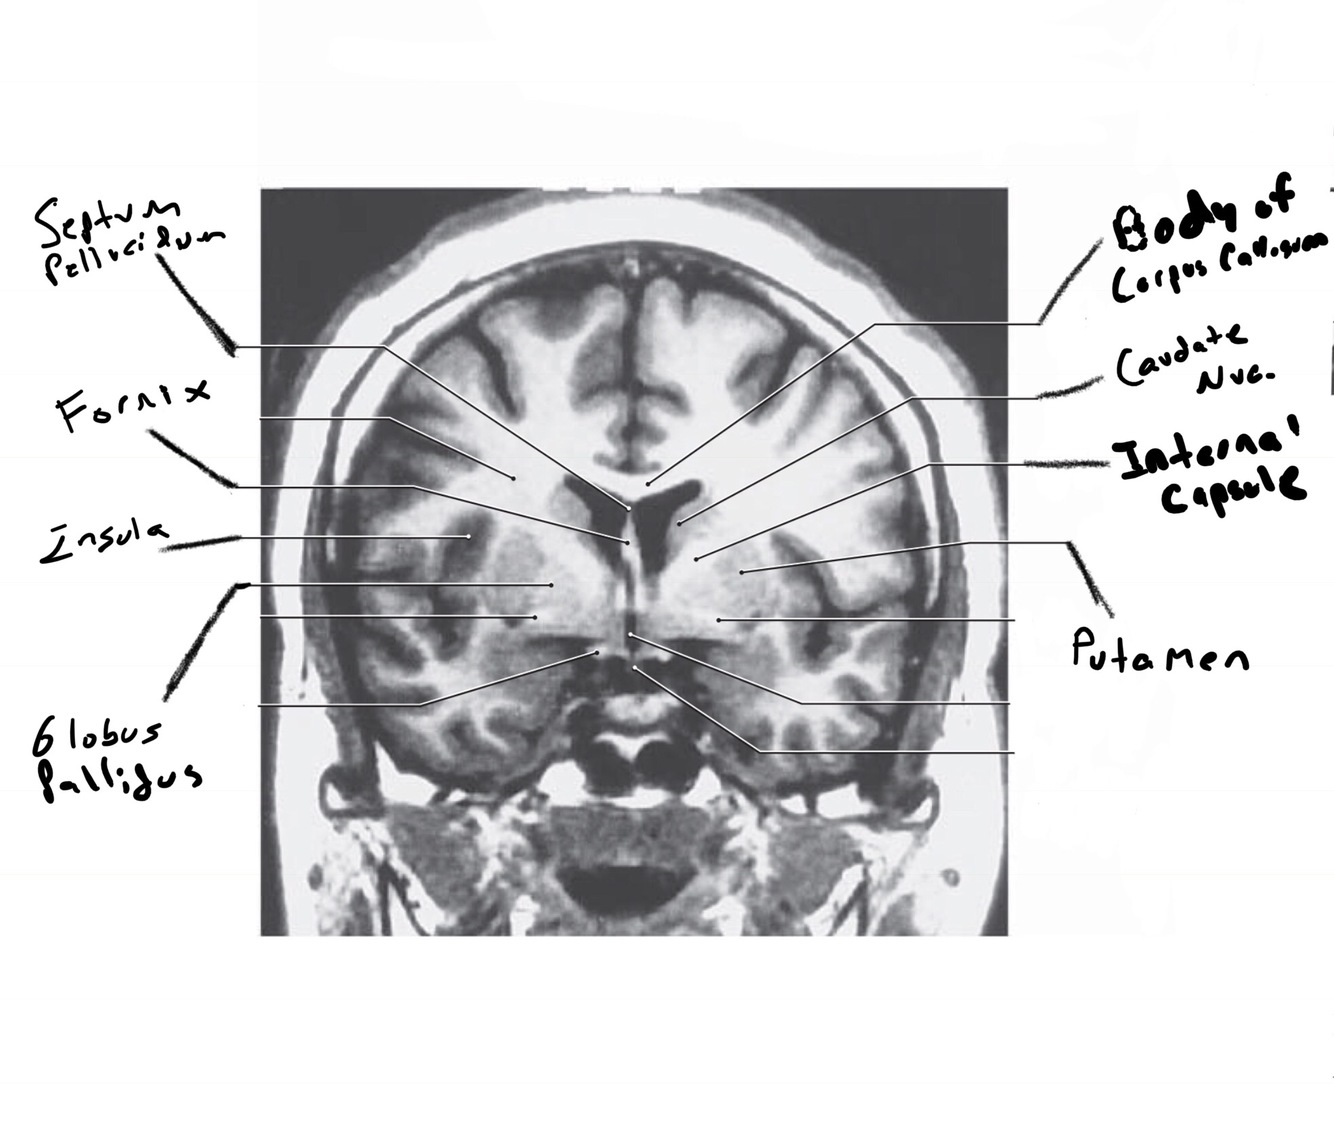

The structure indicated by the red line is?

other format too much work….